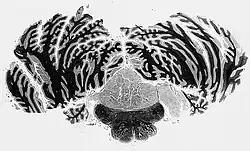

Micrograph of a subependymoma showing the characteristic clustering of nuclei. H&E stain.

The diagnosis is based on tissue, e.g. a biopsy. Histologically subependymomas consistent of microcystic spaces and bland appearing cells without appreciable nuclear atypia or mitoses. The nuclei tend to form clusters.